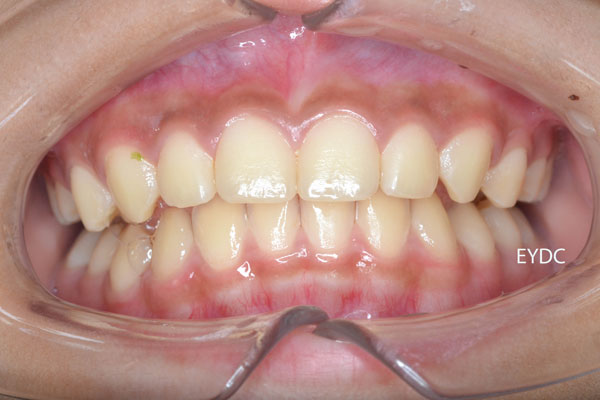

11才7ヶ月。これで完成です。もう装置は付けなくてかまいません。歯並び育成期間は6年でした。熱意をもって通院してくれたお母さんとご本人のがんばりでこんなにきれいになりました。愛くるしくてカワイイお顔をお見せできないのがとっても残念です。この後は経過観察に入ります。